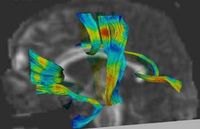

Joint Registration and Segmentation of DWI Fiber TractographyThe goal of this work is to jointly register and cluster DWI fiber tracts obtained from a group of subjects. More... |

DTI Fiber Clustering and Fiber-Based AnalysisThe goal of this project is to provide structural description of the white matter architecture as a partition into coherent fiber bundles and clusters, and to use these bundles for quantitative measurement. More... |

Fiber Tract Modeling, Clustering, and Quantitative AnalysisThe goal of this work is to model the shape of the fiber bundles and use this model description in clustering and statistical analysis of fiber tracts. More... |